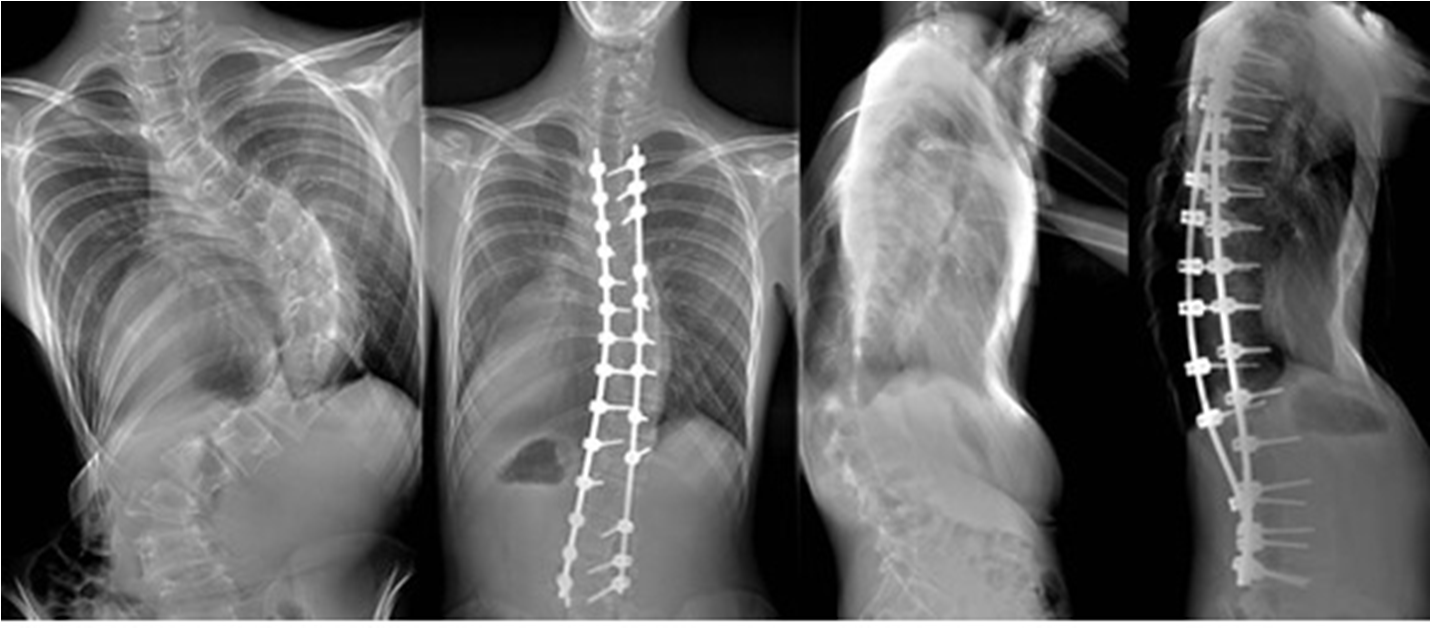

수술적 치료

Cobb's각이 40도 이상일때 시도하며 키의 성장이 남아있고 측만증이 급속히 악활 될 때 교정력 60~70%를 목표로 수술을 시행 한다. 수술후 수술부위는 성장이 멈추고 구부리고 펴는 기능을 상실하게 된다.